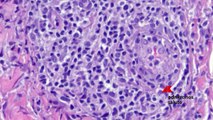

00:13è la prevenzione dei tumori della sfera genitale femminile, in particolare del carcinoma della

00:22cervice. Un carcinoma che unitamente a quello del laringe nei maschi e del pene nei maschi

00:31potrebbe essere completamente azzerato in Italia se la vaccinazione delle nostre donne